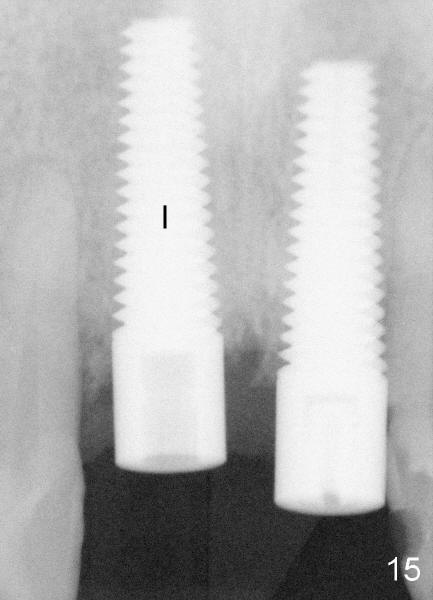

Fifty-five-year-old lady has had pain and swelling associated with #8 for a while in spite of apicoctomy in home country (Fig. 1 and 1' *, > (fistula)).  #9 is prosthodontic failure (Fig.1').  Both teeth are extracted at the same time.